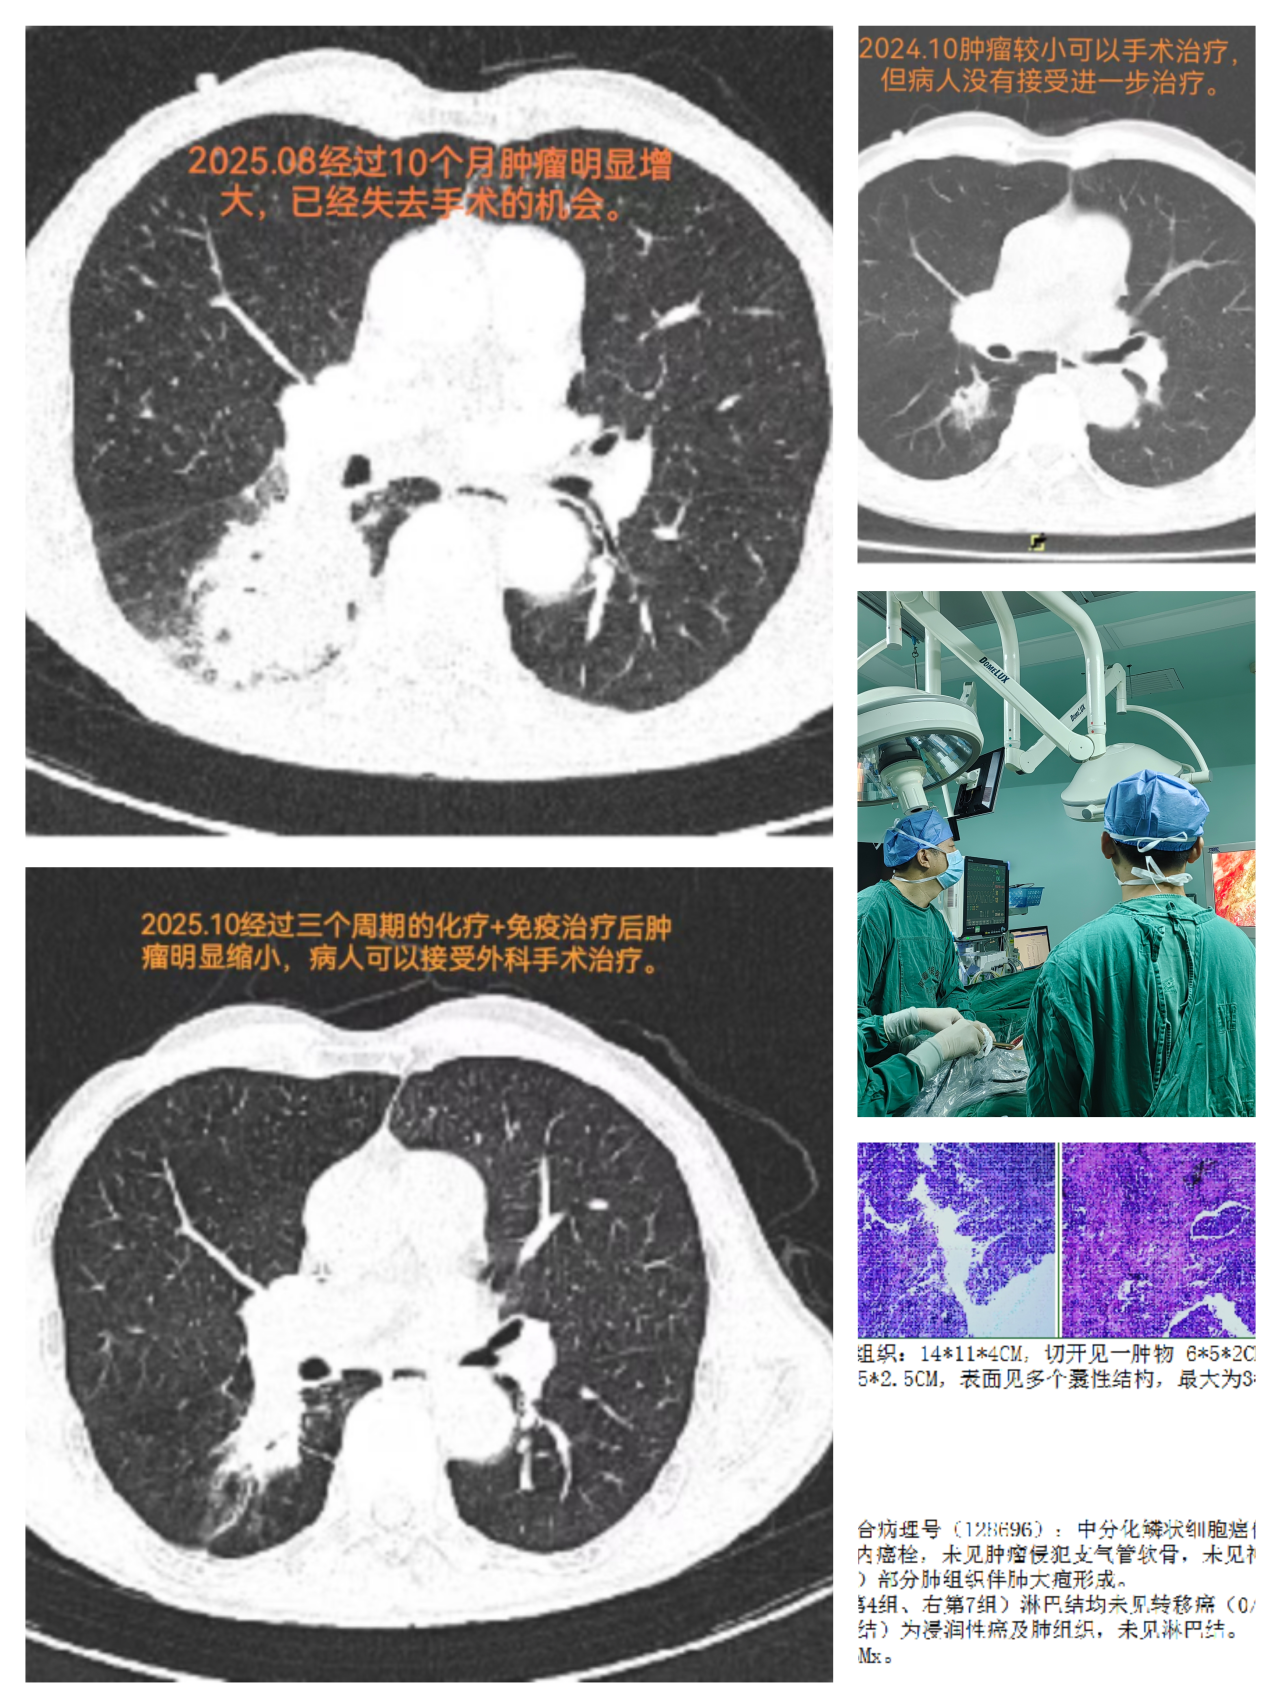

一、胸部肿瘤诊疗:突破技术瓶颈,提升救治能力 高龄食管癌手术自主完成 面对高龄患者手术高风险挑战,科室独立完成82岁食管癌根治术,全程自主把控手术操作与围术期管理,患者术后恢复良好。此次手术标志着我院胸部外科麻醉、医疗及护理体系日趋成熟,为食管肿瘤患者提供了新的治疗选择。 局部晚期肺癌手术稳步推进 针对局部晚期肺癌患者,科室凭借精准的手术规划与精细化围术期管理,成功完成多例手术,为患者争取了治疗时机与生存机会。 转化治疗策略改善晚期肺癌预后 对于初始不可手术的晚期肺癌患者,对接前沿技术,联合肿瘤科开展化疗联合免疫治疗的“转化治疗”策略,成功缩小肿瘤体积并实现降期,最终通过外科手术完整切除病灶。该案例体现了我院MDT团队协作优势,为晚期肺癌患者开辟“带瘤生存”向“无瘤生存”转化的路径。 后纵隔肿瘤诊疗能力提升 先后完成“后纵隔巨大肿瘤综合治疗”“后纵隔复杂肿瘤外科切除”等手术,推动肿瘤综合治疗水平稳步提升。 二、甲状腺疾病诊疗:微创与美容结合,优化治疗体验 腔镜甲状腺手术实现“无痕化”进展 引进“腋下美容切口”“胸乳入路腔镜手术”等技术治疗甲状腺肿瘤,在保证疗效的同时减少手术创伤,兼顾患者美观需求,标志着科室在微创技术道路上迈出坚实步伐。 复杂胸腺肿瘤微创治疗落地 成功开展“剑突下切口微创胸腺肿瘤切除术”,通过微小切口完成深部肿瘤精准切除,术后患者疼痛轻、恢复快,为胸腺肿瘤患者提供新的治疗选择。 三、乳腺疾病诊疗:精准与人文并重,守护女性健康 乳腺癌一体化诊疗模式逐步完善 科室推进早期乳腺癌保乳手术开展,对晚期乳腺癌实施新辅助治疗后再手术,建立“筛查-诊断-治疗-康复”一体化诊疗模式,让患者在家门口就能享受便捷医疗服务。 四、血管与功能性疾病:微创技术解难题,提升患者满意度 功能性疾病微创治疗优化 在腋臭、手汗症等功能性疾病的微创治疗中,科室采用mini切口无痕手术、胸腔镜下交感神经切断等技术,术后效果明显且疤痕隐蔽;静脉输液港植入为肿瘤患者建立“生命通道”。 下肢静脉曲张治疗技术升级 推广“外科微创下肢静脉曲张治疗+硬化剂注射”等新技术,兼具美容、高效优势,对晚期合并溃疡患者效果明显。 五、多学科协作(MDT):强强联合,攻克复杂病例 高危复杂病例协作救治成功 面对颈部巨大肿物压迫导致顽固性高血压、心脏功能恶化的高危患者,科室联合心血管内科、麻醉科组建MDT团队,术前植入临时起搏器保障心脏安全,术中全程严密监护,最终精准切除肿瘤。该案例体现了我院在颈部神经血管危险区多学科协作的能力。 肺结节MDT诊疗方案落地 健全肺结节多学科诊疗(MDT)团队,优化定向追踪随访机制。对中高位风险患者,利用设备和技术优势进行结节特殊“靶扫描”,提高诊断准确率,为后续精准诊疗奠定基础。 回望2025,胸甲状腺乳腺血管外科在多个重点领域的进展,让患者切实感受到“大病不出县”的便利。未来,科室将继续秉持“以患者为中心”的理念,深耕技术创新,强化团队协作,在守护生命的征程上勇毅前行,为区域医疗发展贡献力量。